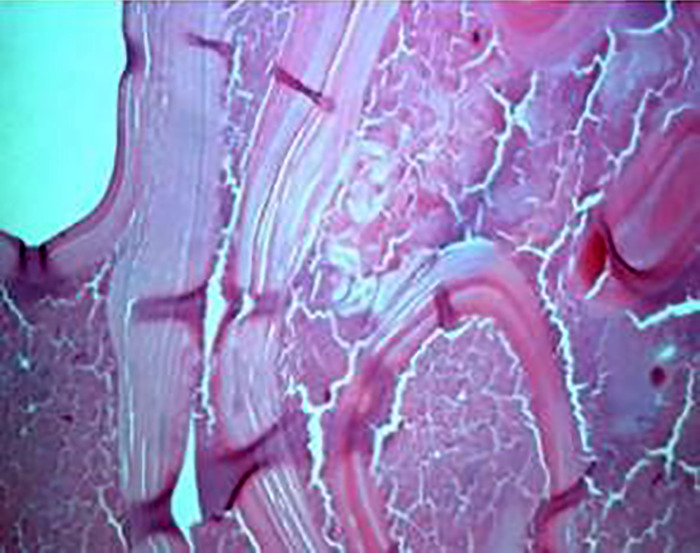

如果不及时诊断和治疗,包虫病破裂可导致腹内囊性包虫病的播散性发展。过敏性休克是囊肿破裂的明确指征。该临床病例为一名患有播散性囊性包虫病的年轻运动员,于2023年在哈萨克斯坦Syzganov国家外科科学中心进行了调查。该疾病在运动训练期间腹部运动损伤后逐渐发展,并伴有过敏性休克的模糊迹象。在接下来的2年里,腹腔棘球蚴病无症状。囊性包虫病的临床表现是在过去10-12周内逐渐发展起来的,表现为沉闷、腹痛、乏力、出汗、恶心、食欲不振、体重减轻。该病的亚急性表现与急性阑尾炎相似。诊断性剖腹检查显示腹腔内有大量囊性形成,需要鉴别诊断是否为弥散性腹结核伴肠系膜淋巴结损害。然而,对寄生虫的仪器验证,加上肺外结核的形态学排除,使得有可能建立一种播散性囊性包虫病。患者接受了膀胱切除术,出院时情况良好,并被告知疾病复发的可能性。总之,在高流行区,建议对所有腹部运动损伤进行棘球蚴病免疫检测,而不考虑是否存在过敏性休克症状。

Rupture of a hydatid cyst can lead to the development of a disseminated form of intra-abdominal cystic echinococcosis if not diagnosed and treated promptly. Anaphylactic shock is a definite indication of cyst rupture. The presented clinical case was a young athlete with a disseminated form of cystic echinococcosis, which was investigated in 2023 at the Syzganov National Scientific Center for Surgery of Kazakhstan. The disease developed gradually following a sports injury to the abdomen during sports training and was accompanied by blurred signs of anaphylactic shock. In the next 2 years, echinococcosis of the abdominal cavity was asymptomatic. The clinical manifestation of cystic echinococcosis developed gradually over the last 10-12 weeks, in the form of dull, painful abdominal pain, malaise, weakness, sweating, nausea, poor appetite, and weight loss. Subacute manifestations of the disease resembled those of acute appendicitis. A diagnostic laparotomy revealed an abundance of cystic formations in the abdominal cavity, necessitating a differential diagnosis between a disseminated form of abdominal tuberculosis with damage to the mesenteric lymph nodes. However, instrumental verification of the parasite, together with the morphological exclusion of the extrapulmonary form of tuberculosis, made it possible to establish a disseminated form of cystic echinococcosis. The patient underwent a cystectomy, was discharged in satisfactory condition, and was informed about the possibility of disease recurrence. In conclusion, in hyperendemic zones, it is recommended to carry out immunological testing for echinococcosis on all abdominal sports injuries, independent of the presence of anaphylactic shock symptoms.